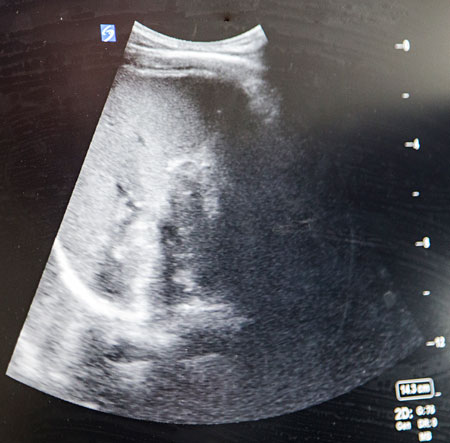

Här är lungan, säger Nina Moeini, som vinklat ultraljudsproben för att se bättre på skärmen innan hon systematiskt jobbar sig igenom undersökningsprotokollets övriga punkter hos det tänkta traumafallet – i själva verket en oskadd frivillig modell.

Mjälten, levern och höger njure. Diafragma, urinblåsan och lungsäcken. Och så hjärtat, precis som protokollet EFAST – utvidgad fokuserad bedömning med ultraljud vid trauma – föreskriver.

– Snyggt! Fyra minuter, där kapade du en och en halv minut på en träningsomgång, coachar Leo Silvén Möller, ST-läkare i internmedicin, när Nina Moeini lägger ifrån sig proben efter att varken ha hittat

fri vätska runt organen eller vätska i hjärtsäcken.

På akuten är patientnära ultraljud en enorm tillgång, anser Nina Moeini, ST-läkare i akutsjukvård. Här guidas hon genom ett tänkt traumafall av Leo Silvén Möller, ST-läkare i internmedicin som i flera år arbetat för att få till S:t Görans ultraljudsakademi. Foto: Martina Holmberg